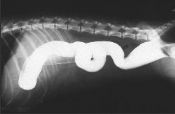

Barium sulfate (type I) is used in the conventional contrast examination of gastrointestinal tract. With an average diameter of 0.85-1.0 micron, the product is featured by fine and uniform particles, good adhesion and stability.

A fine white powder used as a pigment and as a contrast medium in x-ray photography of the digestive tract.